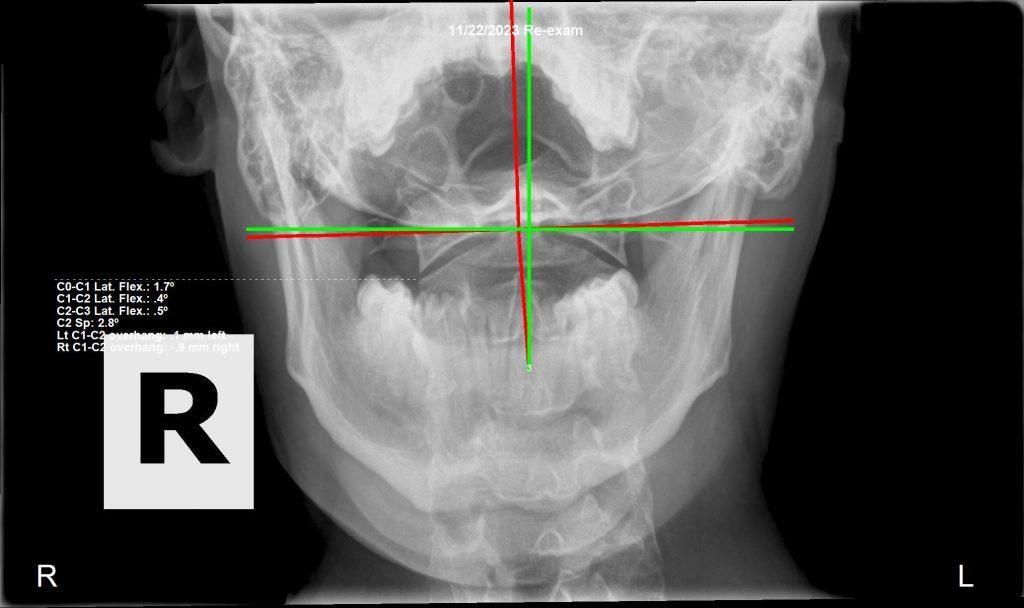

Follow-up cervical X-ray — spinal correction progress

After 3 Months of Care